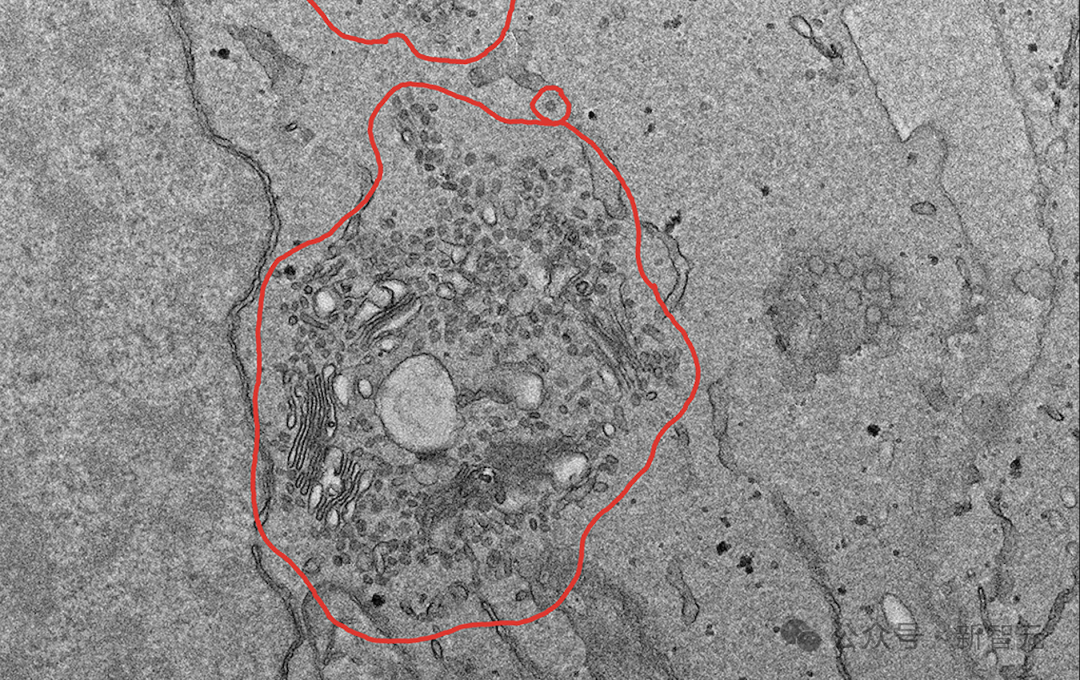

如下,是一个典型的VCT问题,描述了一个场景,并且只能通过视觉信息解决,最后从提供的7个答案陈述中确定哪些是正确的。